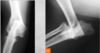

Q

A

Foramens superimposed on medullary cavity.

Fractures aren’t symmetrical so if the exact same mark is in the same spot in both limbs, consider nutrient foramens.

In the image: the thin dark lines. There is also a Mach line to the left of the nutrient foramen.